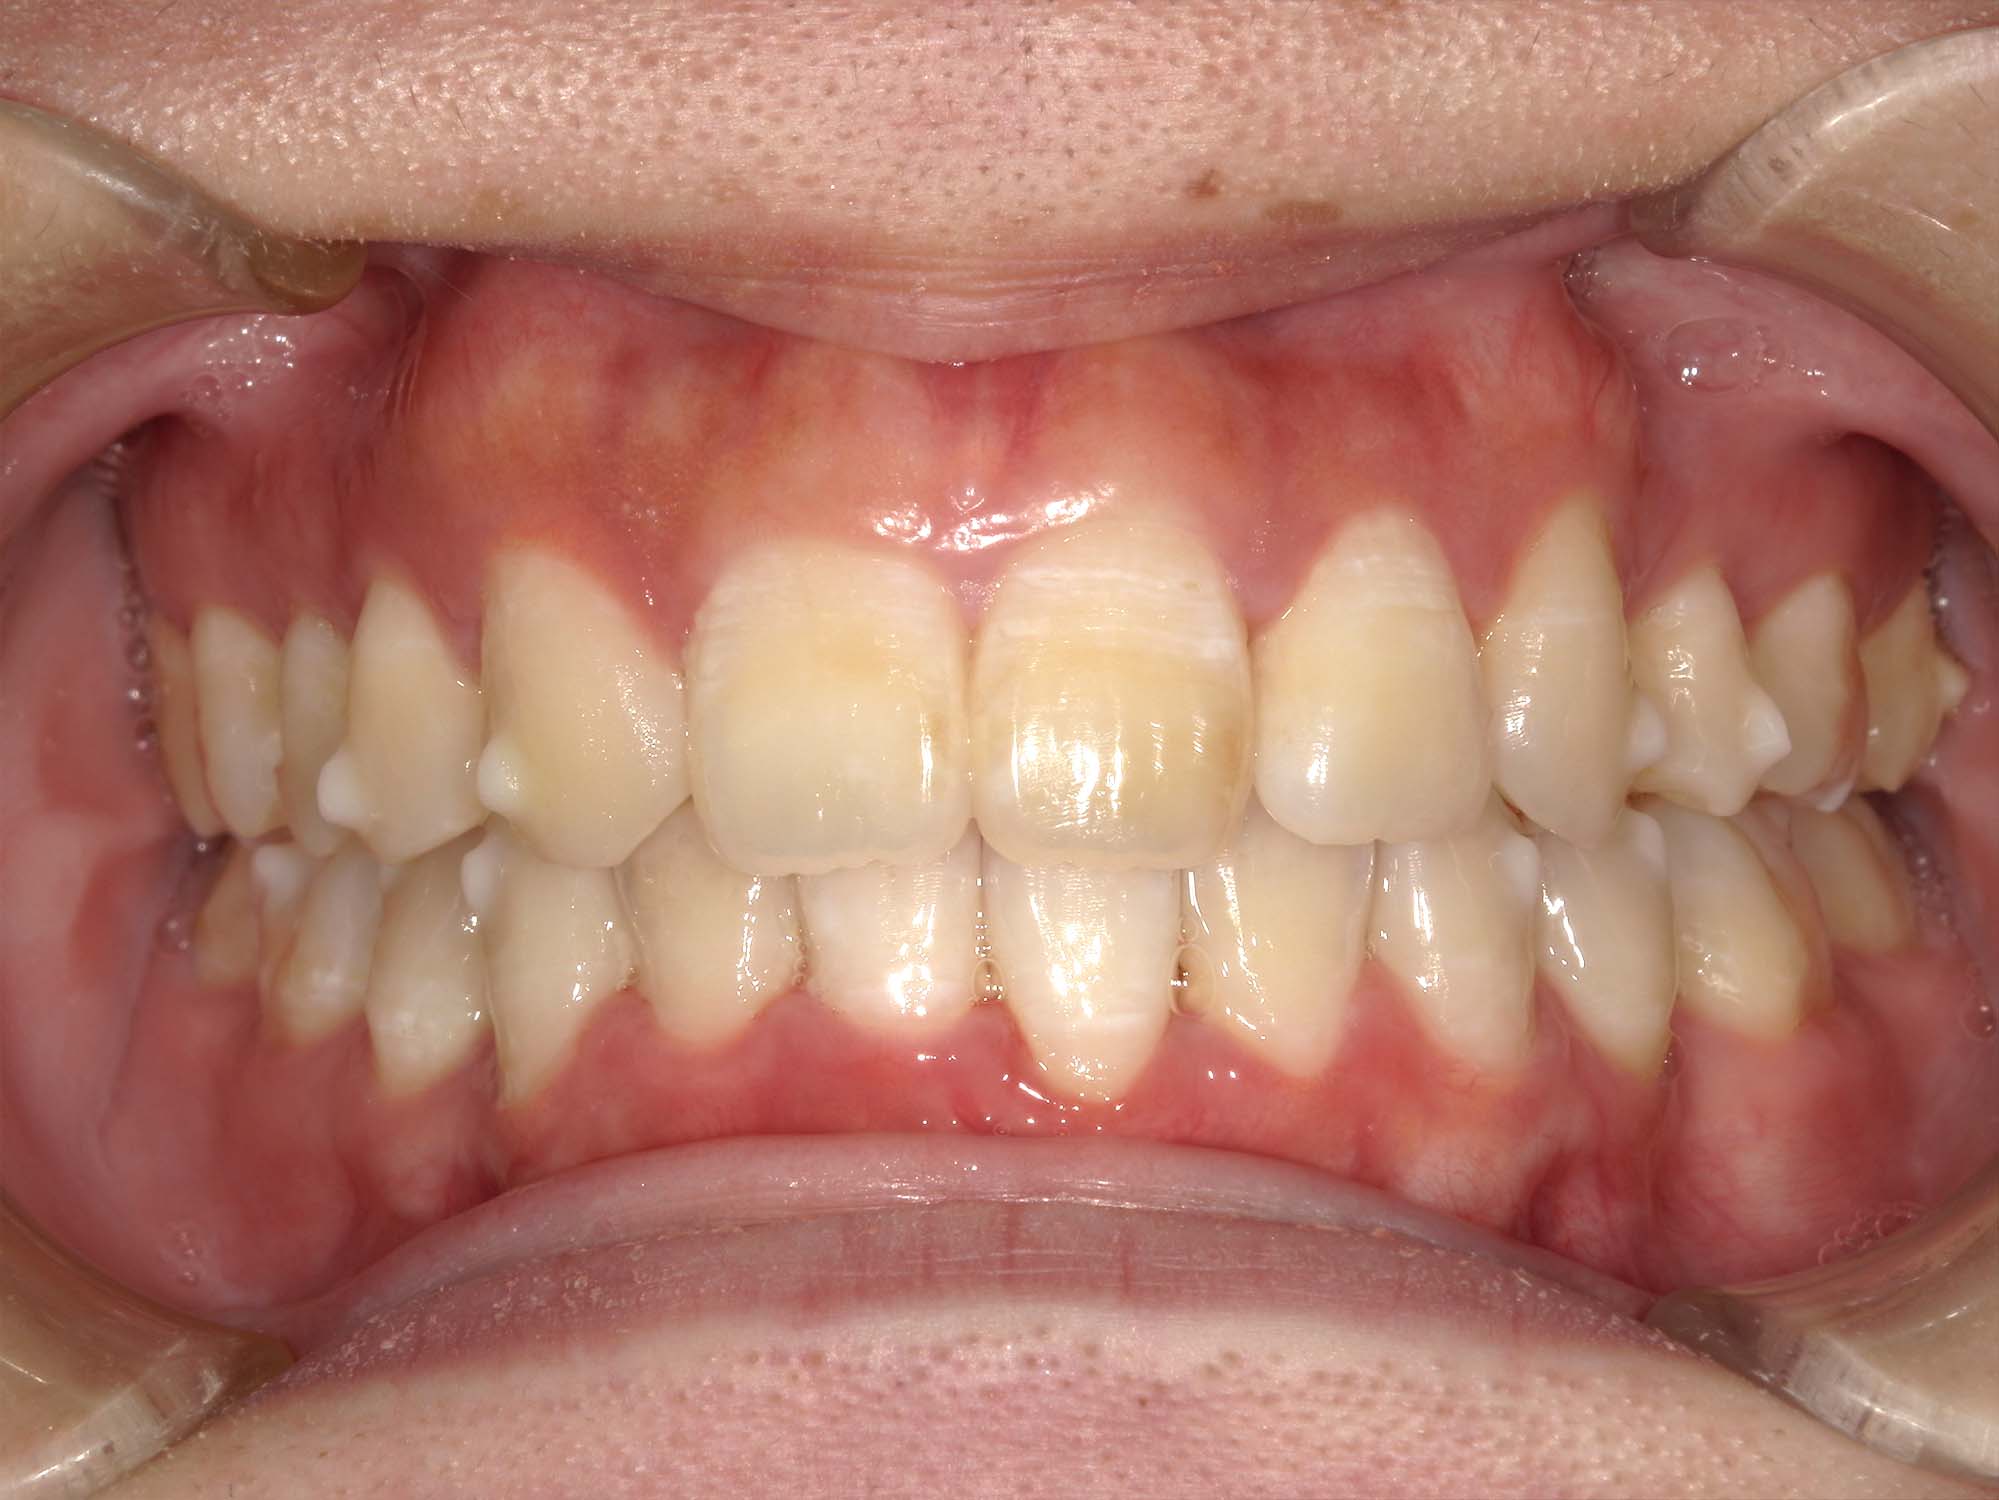

| 年齢・性別 | – |

|---|---|

| 主訴 | 叢生が気になる |

| 治療期間・回数 | 2年 |

| 費用 | 935,000円 |